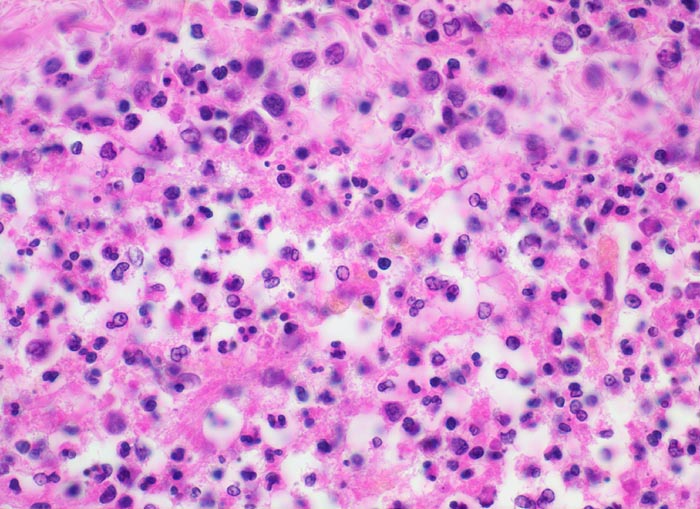

Zytologisch finden sich mehr als 90% neutrophile Granulozyten, ausserdem Fibrin, Makrophagen, degenerierende Zellen, Zelldetritus und manchmal Mikroorganismen. Nach Beginn der Antibiotikatherapie kommt es zu einem raschen Abfall der Zellzahl. Die neutrophilen Granulozyten degenerieren und aktivierte Monozyten beherrschen das Zellbild. Plasmozytoide Lymphozyten und Plasmazellen können dazukommen. In der Reparationsphase verschwinden die Granulozyten, die Anzahl Plasmazellen verringert sich, die Makrophagen sind degeneriert und haben vakuolisiertes Zytoplasma.